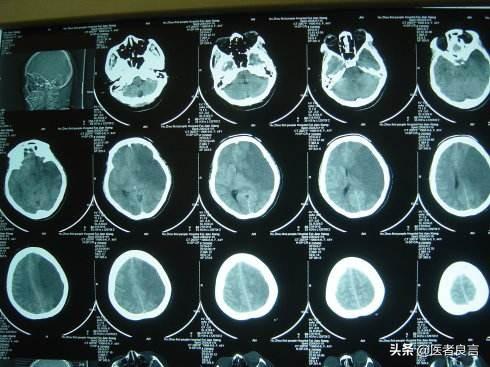

梗塞の場所、同様に梗塞の大きさ、梗塞が脳幹のような非常に重要な部位にある場合は、発症後すぐに呼吸障害を起こし、死に至る可能性がある。一方、梗塞が機能しない部位にある場合は、めまいや不快感程度で済むこともある。

梗塞の大きさは、小さな梗塞では重大な機能障害を伴わないが、大きな脳梗塞では重度の頭蓋内圧亢進、脳腫脹を呈し、脳ヘルニアにより短期間で死亡することもある。

まず、脳梗塞のタイプについて。通常、生存率に関係するのは、梗塞の場所と梗塞部位の大きさである。人間の脳には、意識、呼吸、心拍を司る脳幹と呼ばれる非常に重要な部位があり、椎骨脳底動脈系から栄養を供給されています。 この部位に完全な梗塞が生じると、急速に意識障害が出現し、呼吸停止に移行しやすくなります。また、通常片側の中大脳動脈や内頸動脈の閉塞によって起こる片側の大脳梗塞は、大きな脳梗塞となり、脳幹の重要な中枢を圧迫するほどヘルニア化しやすく、最終的には短時間で死に至る。